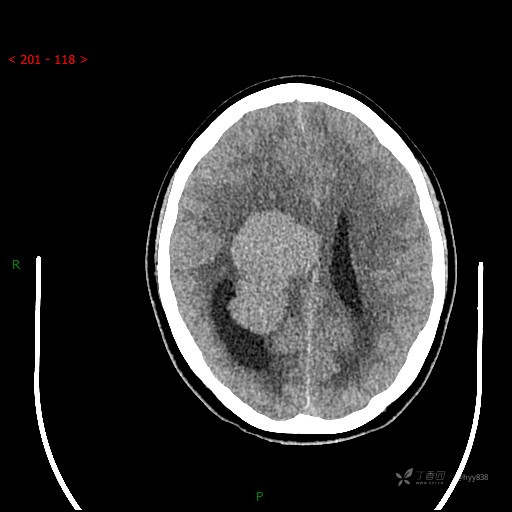

简要病史:患者于1月前无明显诱因出现视物模糊,无明显头痛头晕,无恶心呕吐,无昏迷,无肢体偏瘫等症状,就诊于当地医院头部CT考虑:右侧丘脑、脑室占位。予以对症处置后家属为求进一步诊治来我科,以“颅内占位”收入院。 起病以来,精神、饮食、睡眠欠佳,大小便正常,体力下降,体重无明显变化。

辅助检查:CT MRI

临床诊断:脑室占位

颅脑CT平扫